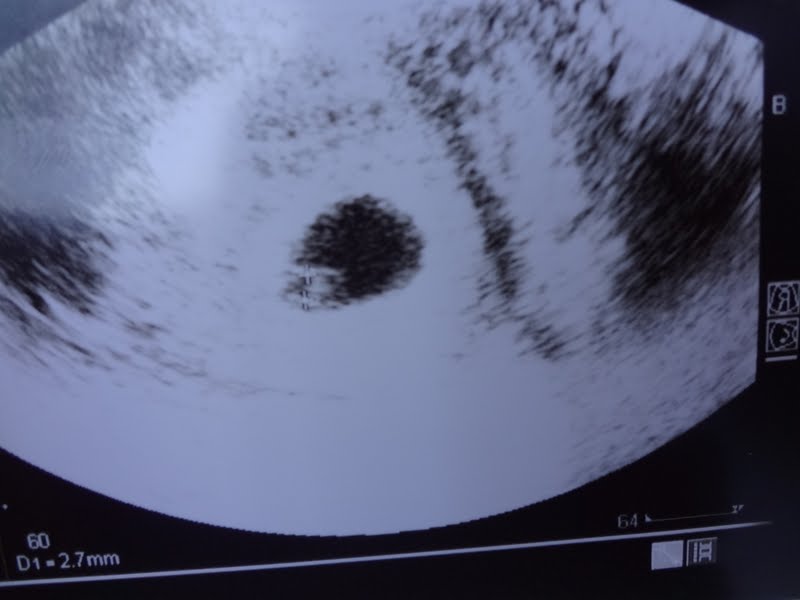

Cá está a primeira foto do nosso bebé.

Ah e não se deixem enganar porque a bolinha que se vê é apenas o saco vitelino. O embrião está aproximadamente entre o tamanho de uma semente de papoila e de uma semente de sésamo.